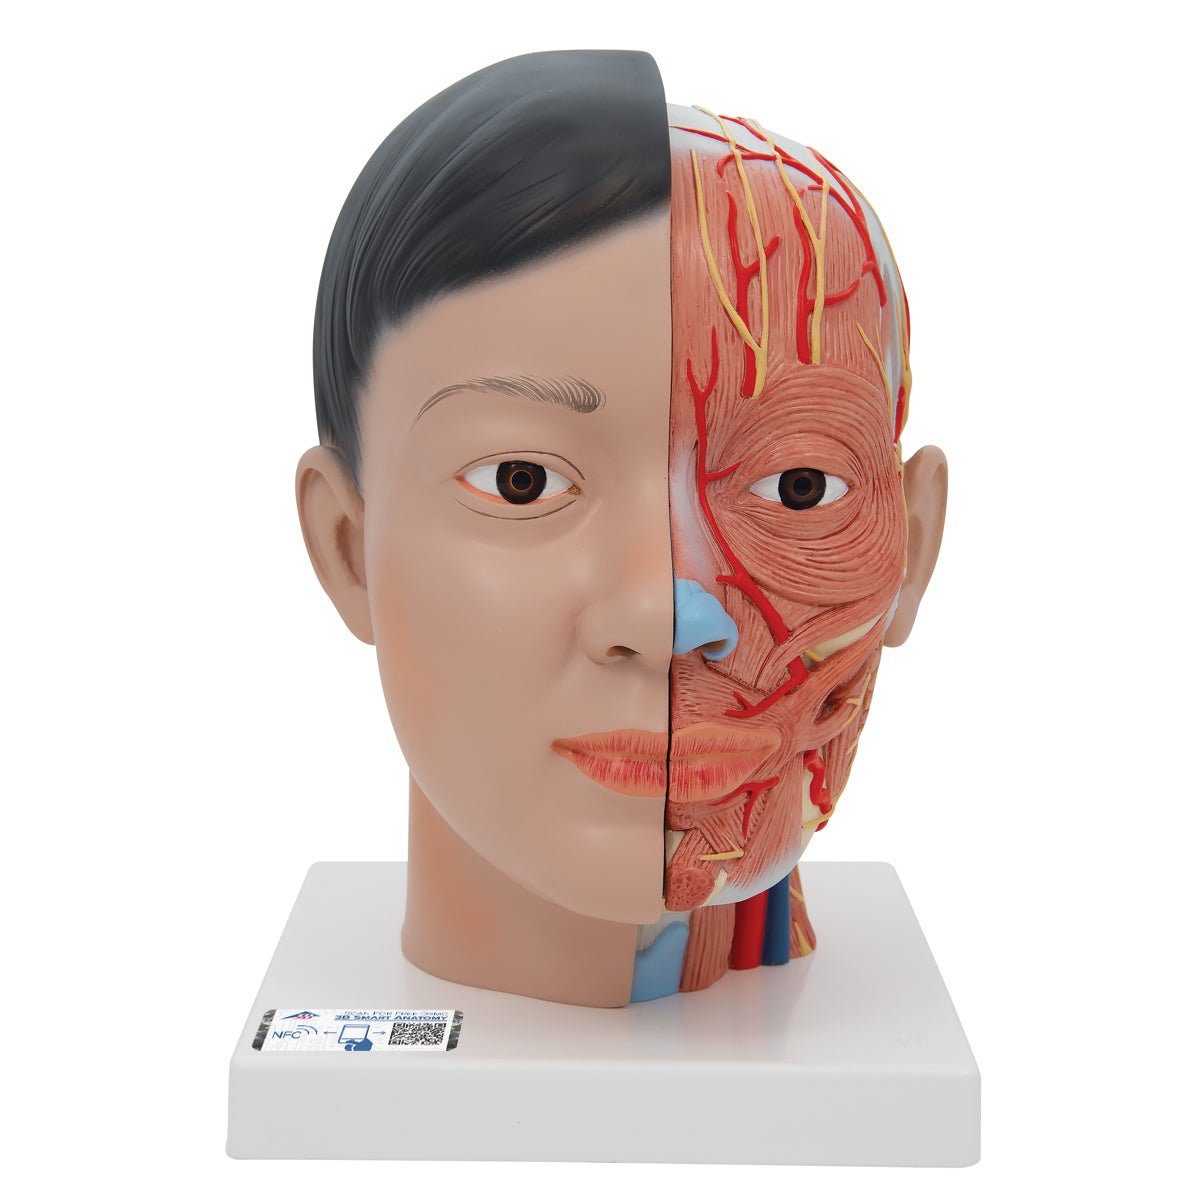

Base of the Head (BS 5/1) · Anatomy models | SOMSO®。Somso Base of the Head, Anatomical Model。Somso Median Section of the Head, Anatomical Model。あやや。SOMSO Anatomical Section Of The Head with MRI Imaging。。写真のように細かなパーツにまで分解できます。Somso Head with Muscles, Anatomical Model。欲しい方はコメントください。SOMSO Nerves and Blood-Vessels on the facial Skull。SOMSO Model of the Head Anatomy Model | Anatomy Warehouse。somso-head-and-neck-model-bs3-。大脳鎌付きの頭部模型です。Model of the Head | Nerves / Blood-Vessels | Head / Neck。SOMSO Half of the Head – GTSimulators.com。リアリティのあるものが欲しい方は是非。ちなみに、ヒト頭部骨標本(本物: 下顎、歯牙も全て揃っています)もあります。SOMSO Model of the Head - Natural size – GTSimulators.com。SOMSO 14-Piece Model of the Skull – GTSimulators.com。本物で頭蓋底などを勉強したい人にお譲りします。(価格は安くはありませんが、、)